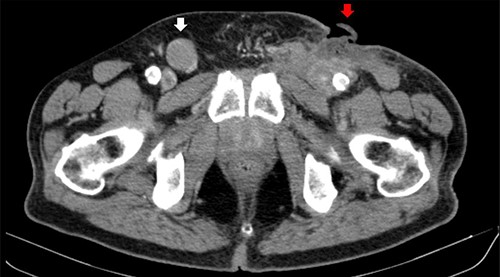

A 73-year-old Caucasian man with a history of hypertension, atrial flutter and Type 2 diabetes mellitus underwent left inguinal hernia repair by Rutkow-Robbins hernioplasty in 2017 without immediate surgical or postoperative complications. In 2021, he reports the appearance of a painless swelling in the left inguinal scar. The patient was medicated with antibiotics without improvement and was sent to the General Surgery consultation with the diagnosis of inguinal mesh rejection. Upon observation by General Surgery, the patient had an ulcerated area of the medial portion of the scar, measuring 1 × 2 cm, with drainage of seropurulent content and surrounding erythema, interpreted as the external orifice of a fistulous tract. The diagnosis of late mesh rejection was maintained, and the patient underwent prosthesis removal without hernia repair. During surgery, extensive peri-mesh fibrosis was found but without apparent signs of infection. The scar was removed en bloc including the ulcerated area and sent for anatomopathological examination. The surgery was uneventful and the patient was discharged. Histological examination (Figs 1–3) revealed extensive involvement of the dermis and hypodermis by a high-grade non-Hodgkin lymphoproliferative process with characteristics of diffuse large-cell B lymphoma, which focally conditions epidermal ulceration. The immunohistochemical study showed diffuse staining for CD20, MUM-1 and CD10, with weak and heterogeneous staining in ~40–50% of neoplastic cells for C-MYC and 80–90% of the same population cell for Ki-67. Immunostains for CD30 were not observed and with anti-CD3 and anti-CD5 antibodies, only marking of scattered rare reactive T lymphocytes was observed. Finally, the neoplastic cell population had no staining for bcl2, but diffuse staining for bcl6. Upon reassessment, the patient had wound dehiscence with an extensive ulcerated area (Fig. 4) and was oriented to hematology. Bone marrow biopsy, myelogram and flow cytometry were normal and computerized tomography of the neck, chest, abdomen and pelvis revealed a right inguinal adenopathy (Fig. 5). The patient was staged as IIa and proposed for systemic treatment with rituximab, cyclophosphamide, doxorubicin, vincristine and prednisolone (R-CHOP).

Computerized tomography image. Right inguinal adenopathy (white arrow) and PCBCL (red arrow).